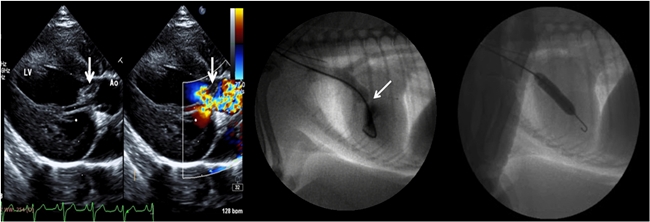

심장초음파 영상 (왼쪽)과 심장조영(가운데)을 통하여 확인한 후,

풍선카테터를 이용하여 협착부위를 개선시키는 영상(오른쪽)

폐동맥협착증을 앓고 있던 1년 9개월령 프렌치불독 품종 환견과 대동맥하협착증을 앓고 있던 9개월령 포메라니언 품종 환견은 선천적 심장질환으로 인해 어렸을 때부터 기절, 운동불내성, 청색증 등의 증상으로 고통 받았다.